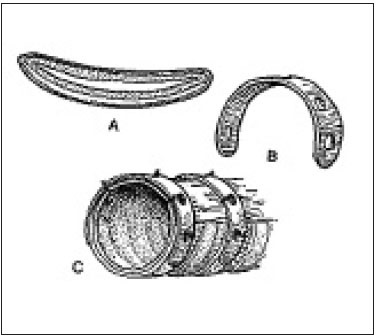

Endoluminális helyreállítása légcső keresztül önmagától táguló stent készült Nitinol (nikkel-titán ötvözet) használt a közelmúltban. Ez protézis eredetileg tervezett bővítése sérült artériák és epeutak emberekben. Az általunk használt biliáris stentek Nitinella, amelyeknek számos előnye van: atraumatikus végei csökkentse annak lehetőségét, traumás légcső fal, nagy szilárdságú ellenállás, jó kapacitás bővítését, könnyen implantáció, radiopak markerek mindkét végén a sztent (ris.11,12).

Mivel a Nitinol hajlékony és rugalmas, és fizikai tulajdonságai hasonlóak a porc, a légcső, a legtöbb önműködő sztentek készült nitinol. Nitinoit stent használunk állandó implantátumot, és ezért nagyon fontos, hogy válassza ki a megfelelő méretet. Az átmérő van kiválasztva viszonyítva a normál rész trachea átmérője. Tartós beültetés, az szükséges, hogy a stentet a nyálkahártya alatti réteg, ez okozza nyomást elhalása az epitéliumban, de nem okoz a migráció a stent, amely irritációt okozhat, és a termelés granulációs szövet vezető légúti elzáródás. A cél az, hogy a légcső túl a többit a sztent és vezetjük be a nyálkahártya alatti réteg. Fokozott nyugalmi tracheális átmérőjű 1-25-1.8 időt biztosít optimális tömörítés. Átmérőjének növelése kétszer vezethet negatív következményekkel jár a sztent behatolás a mélyebb rétegeibe a légcső és a nekrózis (13. ábra).

A telepítés után a stent a légcső ürege, a stent fokozatosan alkalmazkodik az üreg méretét a légcső. Az előnye ennek az eljárásnak, mint a műtéti stabilizálásra ¬sostoyat az, hogy nem invazív, és mindössze 5-10 perc, függően a gyakorlati képesség (ris.14,15).